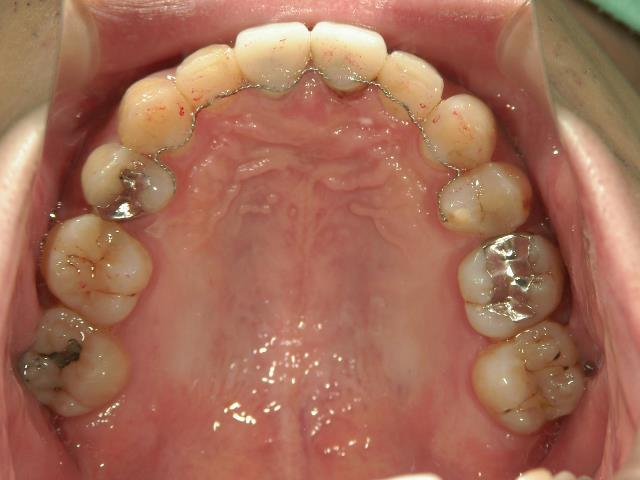

矯正歯科 治療前 上顎の左右4番計2本を抜歯し叢生を改善。

矯正_灰色.pngno.24_8228_治療前_上.jpg矯正_灰色.png